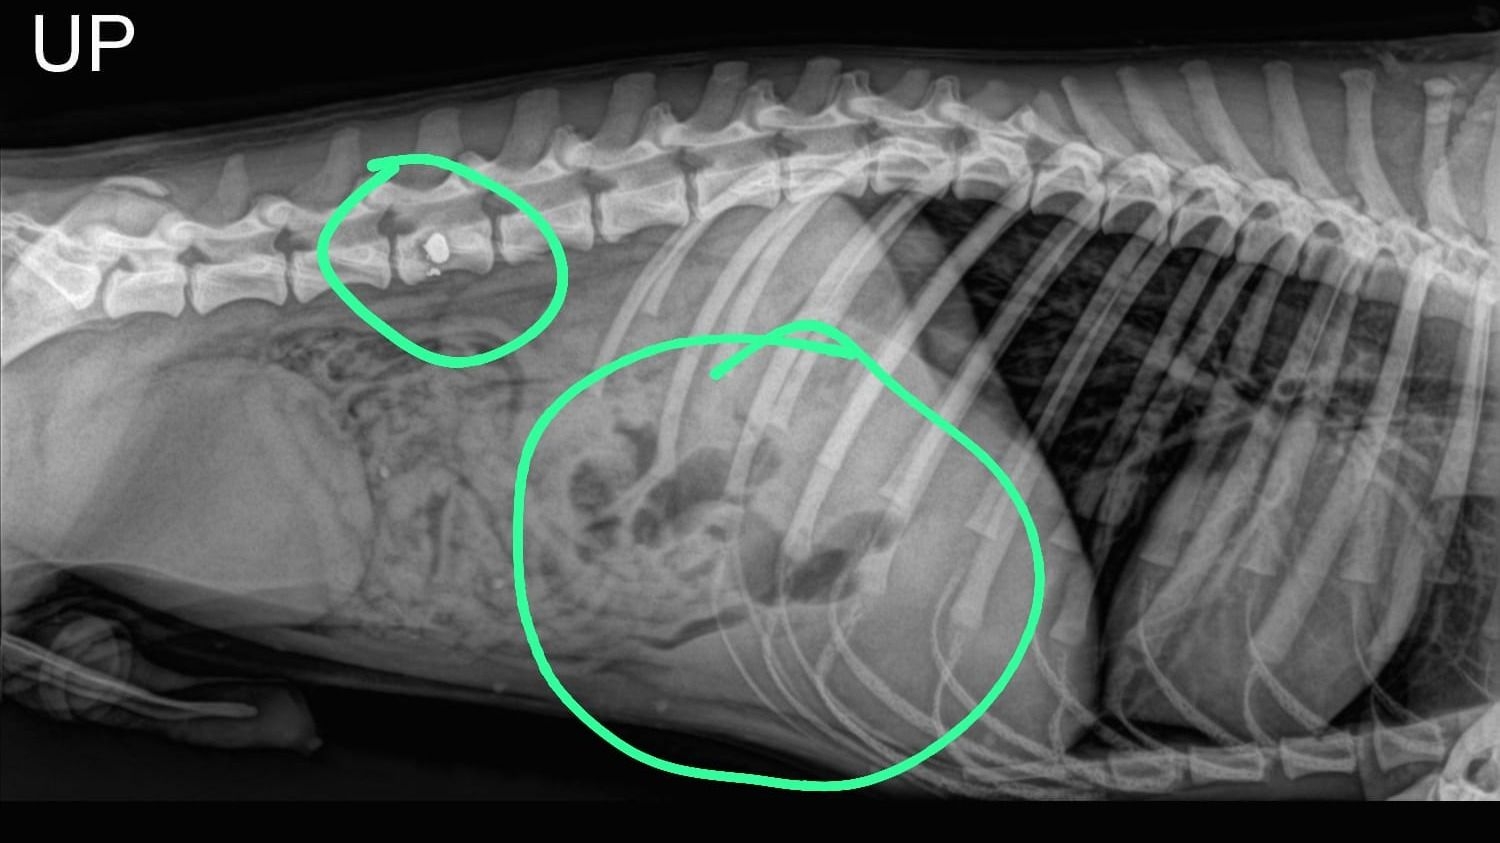

La radiografía arrojó que una bala quedó alojada y la otra entró y salió. Foto: Gentileza

Lamentablemente, en este caso, el perro falleció y fue sepultado a través de un servicio que se encarga de eso. El animal tenía dos orificios de balas, y según el veterinario una se encontraba alojada en la columna vertebral mientras que la otra herida fue de una bala que entró y salió por el tórax del perro callejero.